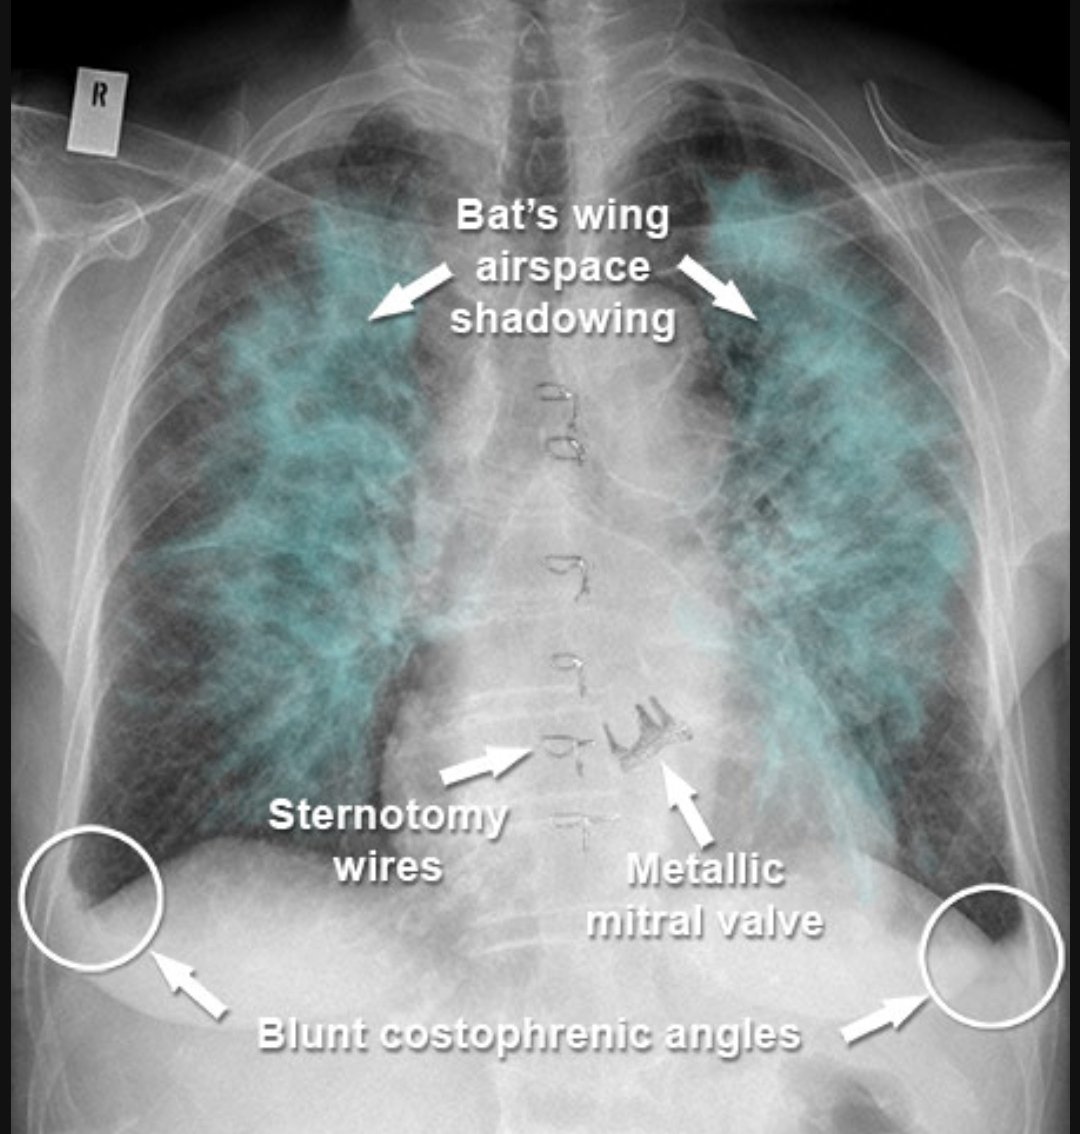

Bat Wing Appearance On Chest X Ray Pulmonary Edema On Chest

Module Title Tutorial Congestive Heart Failure

Pulmonary Oedema Chest X Ray MedSchool

Bat s Wing Or Butterfly Pulmonary Opacities Refer To A Pattern Of